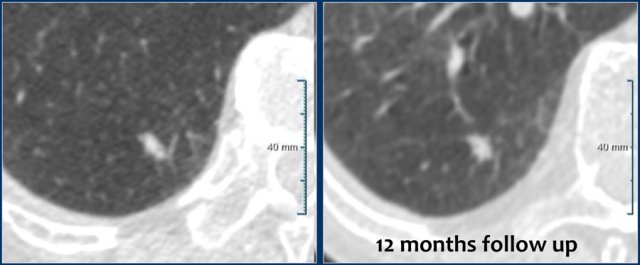

A solitary non-spiculated solid nodule of 7 mm (162 mm3) is shown in the RLL of a 55 year old male without a positive family history, but with some emphysema.

Follow-up showed long term stability with 7 mm (146 mm3) at 12 months.

Patient was discharged from further CT surveillance.